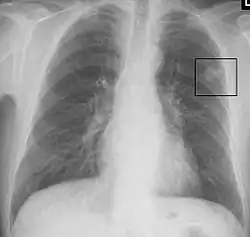

Der Unterschied zwischen der überlagerungsfreien Darstellung in der medizinischen Tomografie und einer Projektionsabbildung ist in den nachfolgenden Abbildungen illustriert. In Projektionsverfahren wie der Radiografie (gewöhnliche Röntgenuntersuchung) wird ein Schattenbild aufgenommen, auf dem sich mehrere Strukturen überlagern, wenn sie im Strahlengang hintereinander liegen. Beispielsweise überlagern beim konventionellen Röntgenbild die Weichteile der vorderen und hinteren Brustwand und die knöchernen Strukturen des Thorax die Lungenstrukturen. Dies würde die Diagnose eines Lungentumors (z. B. Bronchialkarzinom) erschweren. Jedes CT- oder MRT-Schnittbild vom Thorax zeigt dagegen nur eine 0,5 bis 10 mm dicke Schicht, die praktisch überlagerungsfrei ist.

Röntgenbild (Projektionsbild) eines kleinen peripheren Bronchialkarzinoms im linken Oberlappen

Röntgenbild (Projektionsbild) eines kleinen peripheren Bronchialkarzinoms im linken Oberlappen -